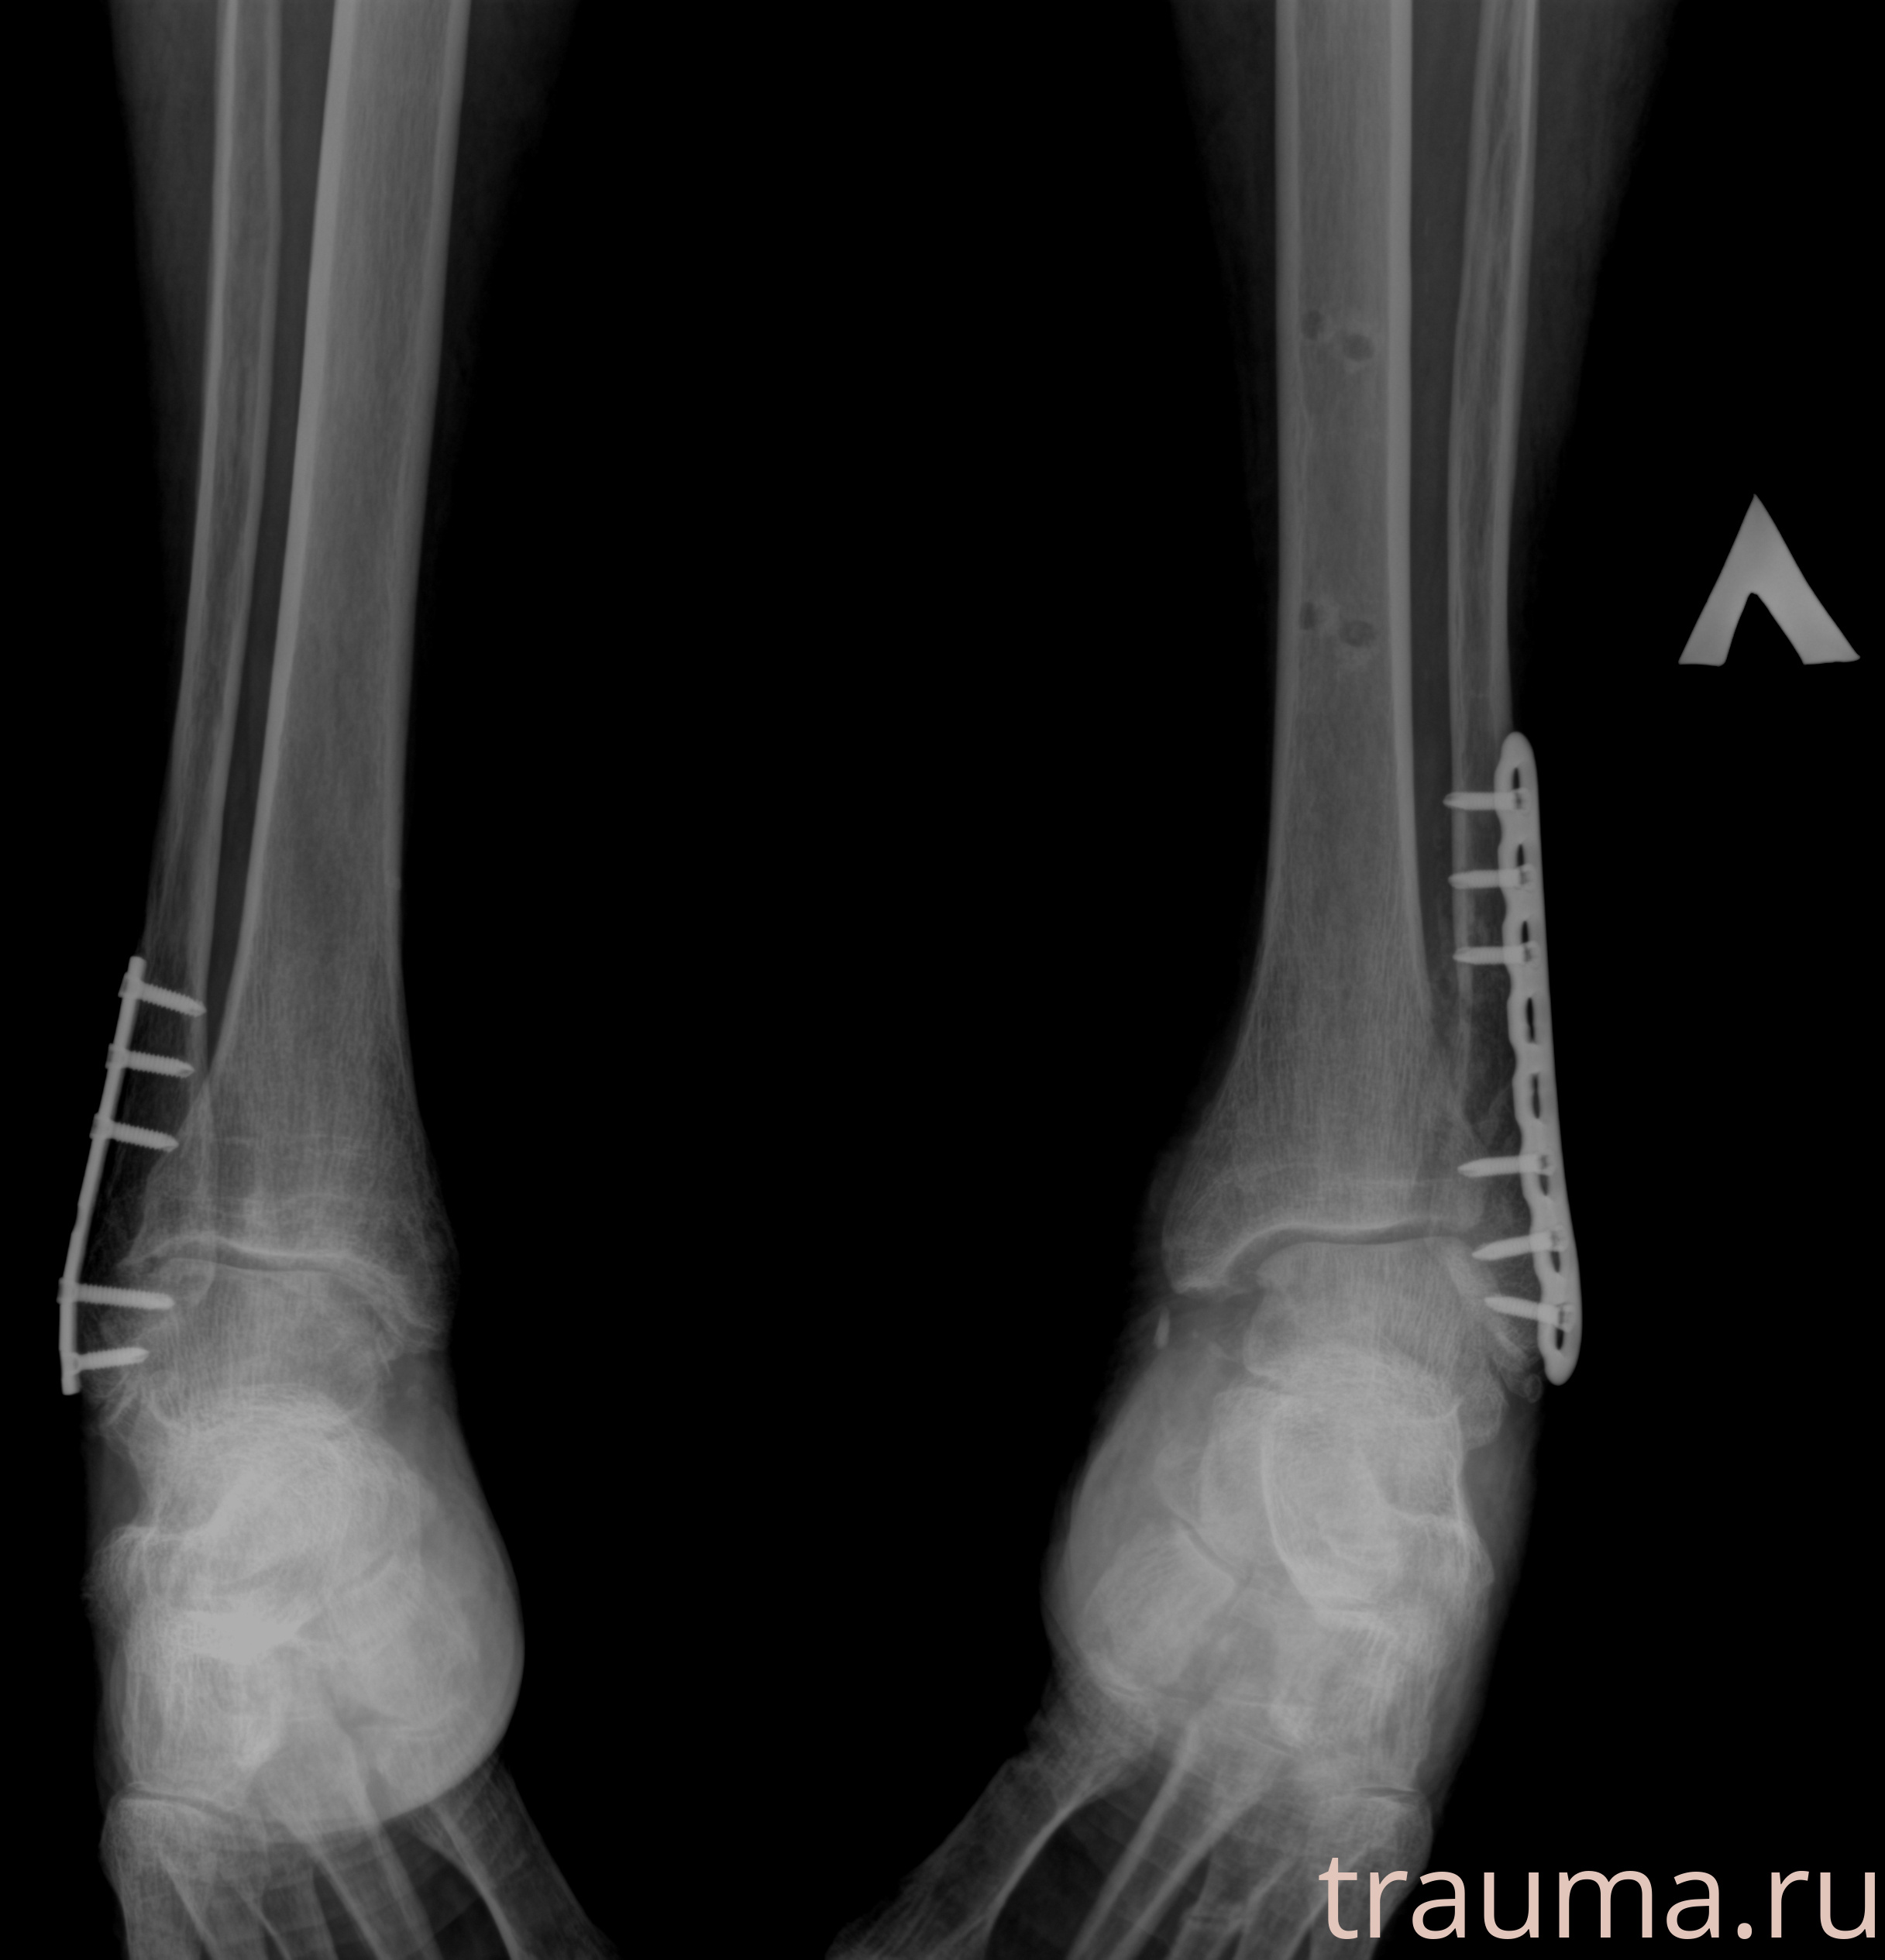

Рентгенограммы